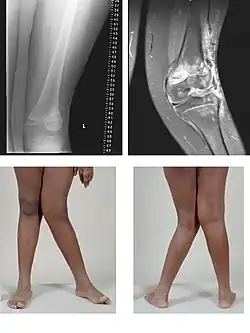

Valgusstellung am Kniegelenk

Am Kniegelenk ist dies eine Abweichung des Unterschenkels nach außen, was einem X-Bein entspricht, wenn die normale X-Stellung (physiologische Valgusstellung) von 7 Grad überschritten ist; dadurch sind die inneren Gelenkanteile oft hervorstehend. Der Fachterminus ist das Genu valgum.

Bei einem X-Bein (Genu valgum) kann dies durch eine vermehrte Belastung des äußeren Gelenkspaltes zu einer außenseitig betonten Valgus-Gonarthrose führen.